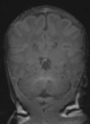

For the preterm infant, the provision of diagnostic measurements of brain compromise is a high priority, in order to minimise the risk of developmental impairment. Amplitude-integrated electroencephalography (aEEG) is used to monitor the functional status of the brain and to observe maturational changes during extrauterine development. Near-infrared spectroscopy (NIRS) enables continuous estimation of cerebral oxygenation. General movements (GM) are part of the spontaneous movement repertoire of newborn infants. The presence, quality and intensity of GM are markers of central nervous system integrity. Quality of GM has emerged as a reliable predictor of neurodevelopmental delay in preterm infants. Cerebral magnetic resonance imaging (MRI), performed at term-equivalent age in all very preterm infants, provides detailed information on the wide spectrum of preterm brain injury and alterations in postnatal brain development in preterm infants (Fig. 1).